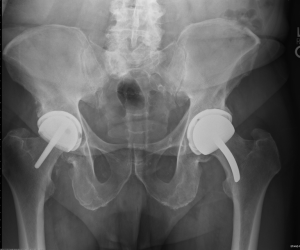

Beginning in 1998, the author has implanted 2,154 highly cross-linked hip resurfacing prostheses in 1,931 patients. Thirty-two patients died and 35 were lost to follow-up. The same inclusion and exclusion criteria were used in this study of polyethylene hip resurfacing as have been used in other studies for metal-on-metal hip resurfacing. It was necessary to have geometry that would allow placement of the acetabular prosthesis with a least 5 mm of medial wall preservation and bone quality that was within the normal range (34,35). The femoral prostheses were cemented in 840 (39%) and uncemented in 1,314 (61%) patients (Figure 3). Follow-up examinations were performed at 8 weeks, 6 months, and annually, and outcomes were assessed using the Modified Harris Hip Score, WOMAC instrument, and UCLA Hip Score (36-38). Follow-up evaluation also included a digital anteroposterior (AP) view radiograph of the pelvis centered over the symphysis (Figure 4), an AP view of the hip centered over the femoral head, and a shoot-through lateral radiograph. High-resolution CT scans with metal-artifact reduction software were performed to look for polyethylene wear in 102 participants when they presented 6–11 years postoperatively (18) (Figure 5).

The follow-up period ranged from 5 to 21 years (median, 9.5 years). Patient demographics are shown in Table 1. The postoperative functional results all improved significantly (Table 2). Eighty percent of the patients achieved a postoperative UCLA score of 8 or greater. The average acetabular component inclination was 41° (range 30° to 53°) and the average anteversion was 15° (range, 0° to 25°). The average femoral anteversion was 13° (range, 0° to 20°). All femoral components were neutral or placed in a valgus orientation with respect to the native femur. Screw fixation was used in 9% of patients when the shell was ≥20% uncovered.